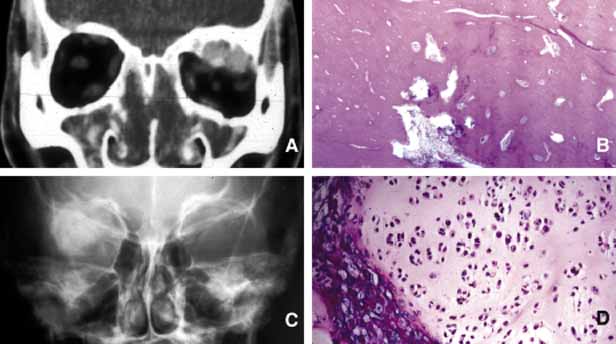

Most of the dermoids are well outlined by ultrasonography because of their anterior location thus making CT or MRI rarely necessary.19 If the dermoid is unusually large or located at the frontal zygomatic suture, CT is necessary to document the relationship of the lesion to the bone before surgical intervention. Rarely, dermoids at the fronto-zygomatic suture may develop dumbbell-shaped lesions partially within the orbit and partially extending into the temporal fossa.20,21 Unusually large superior orbital dermoids particularly those that leak and create granulomatous reaction within adjacent soft tissues may erode the bone and extend into the frontal sinus or the cranium (Fig. 2).

Fig. 2 Dermoid. Different presentations of dermoid (d): superior medial, semi-solid mass pushing the globe down and out (A); a ruptured dermoid causing an inflammatory reaction within adjacent soft tissues (B); a large superior lateral dermoid eroding through the roof of the orbit to extend into the brain (C); extraorbital dermoid within the subcutaneous tissues of the eyebrow (D); gross appearance of the cystic dermoid containing whitish yellow cheesy keratin material intermixed with hair (E); dumbbell dermoid that is present on both sides of the frontozygomatic fissure (F); histopathology of dermoid wall (dw) containing skin appendages, the lumen of the dermoid is lined with stratified squamous epithelium producing keratin (K) (G). ([E] is the courtesy of Amin M. Nasr, MD of Beirut, Lebanon)